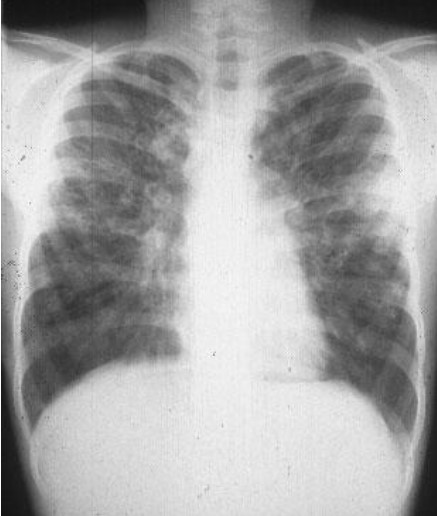

Common X-ray Findings: